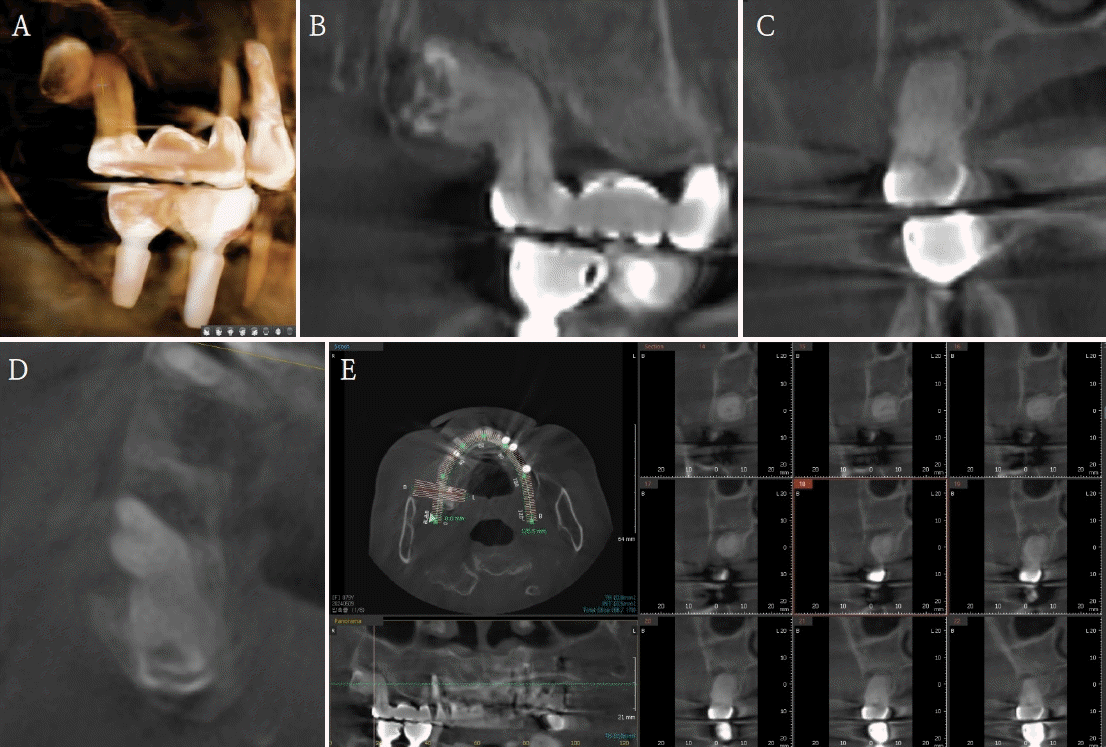

Figure 2.

A. Cone-beam computed tomographic 3-dimensional reconstruction image. B. Panoramic view. C. Cross-sectional view. D. Axial view. E. Cross-sectional image shows that the two teeth are attached to each other and the roots have a bulbous appearance due to hyperproliferated cementum.